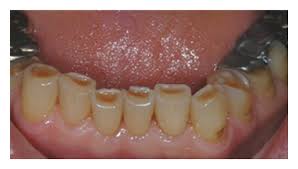

🛑Clinical presentation –

- Appearance of small polished facet on the cusp tip /ridge or slight flattening of the incisal edge

- Tooth discoloration : attrition and erosion of the enamel exposes inner and darker dentine giving a yellower appearance